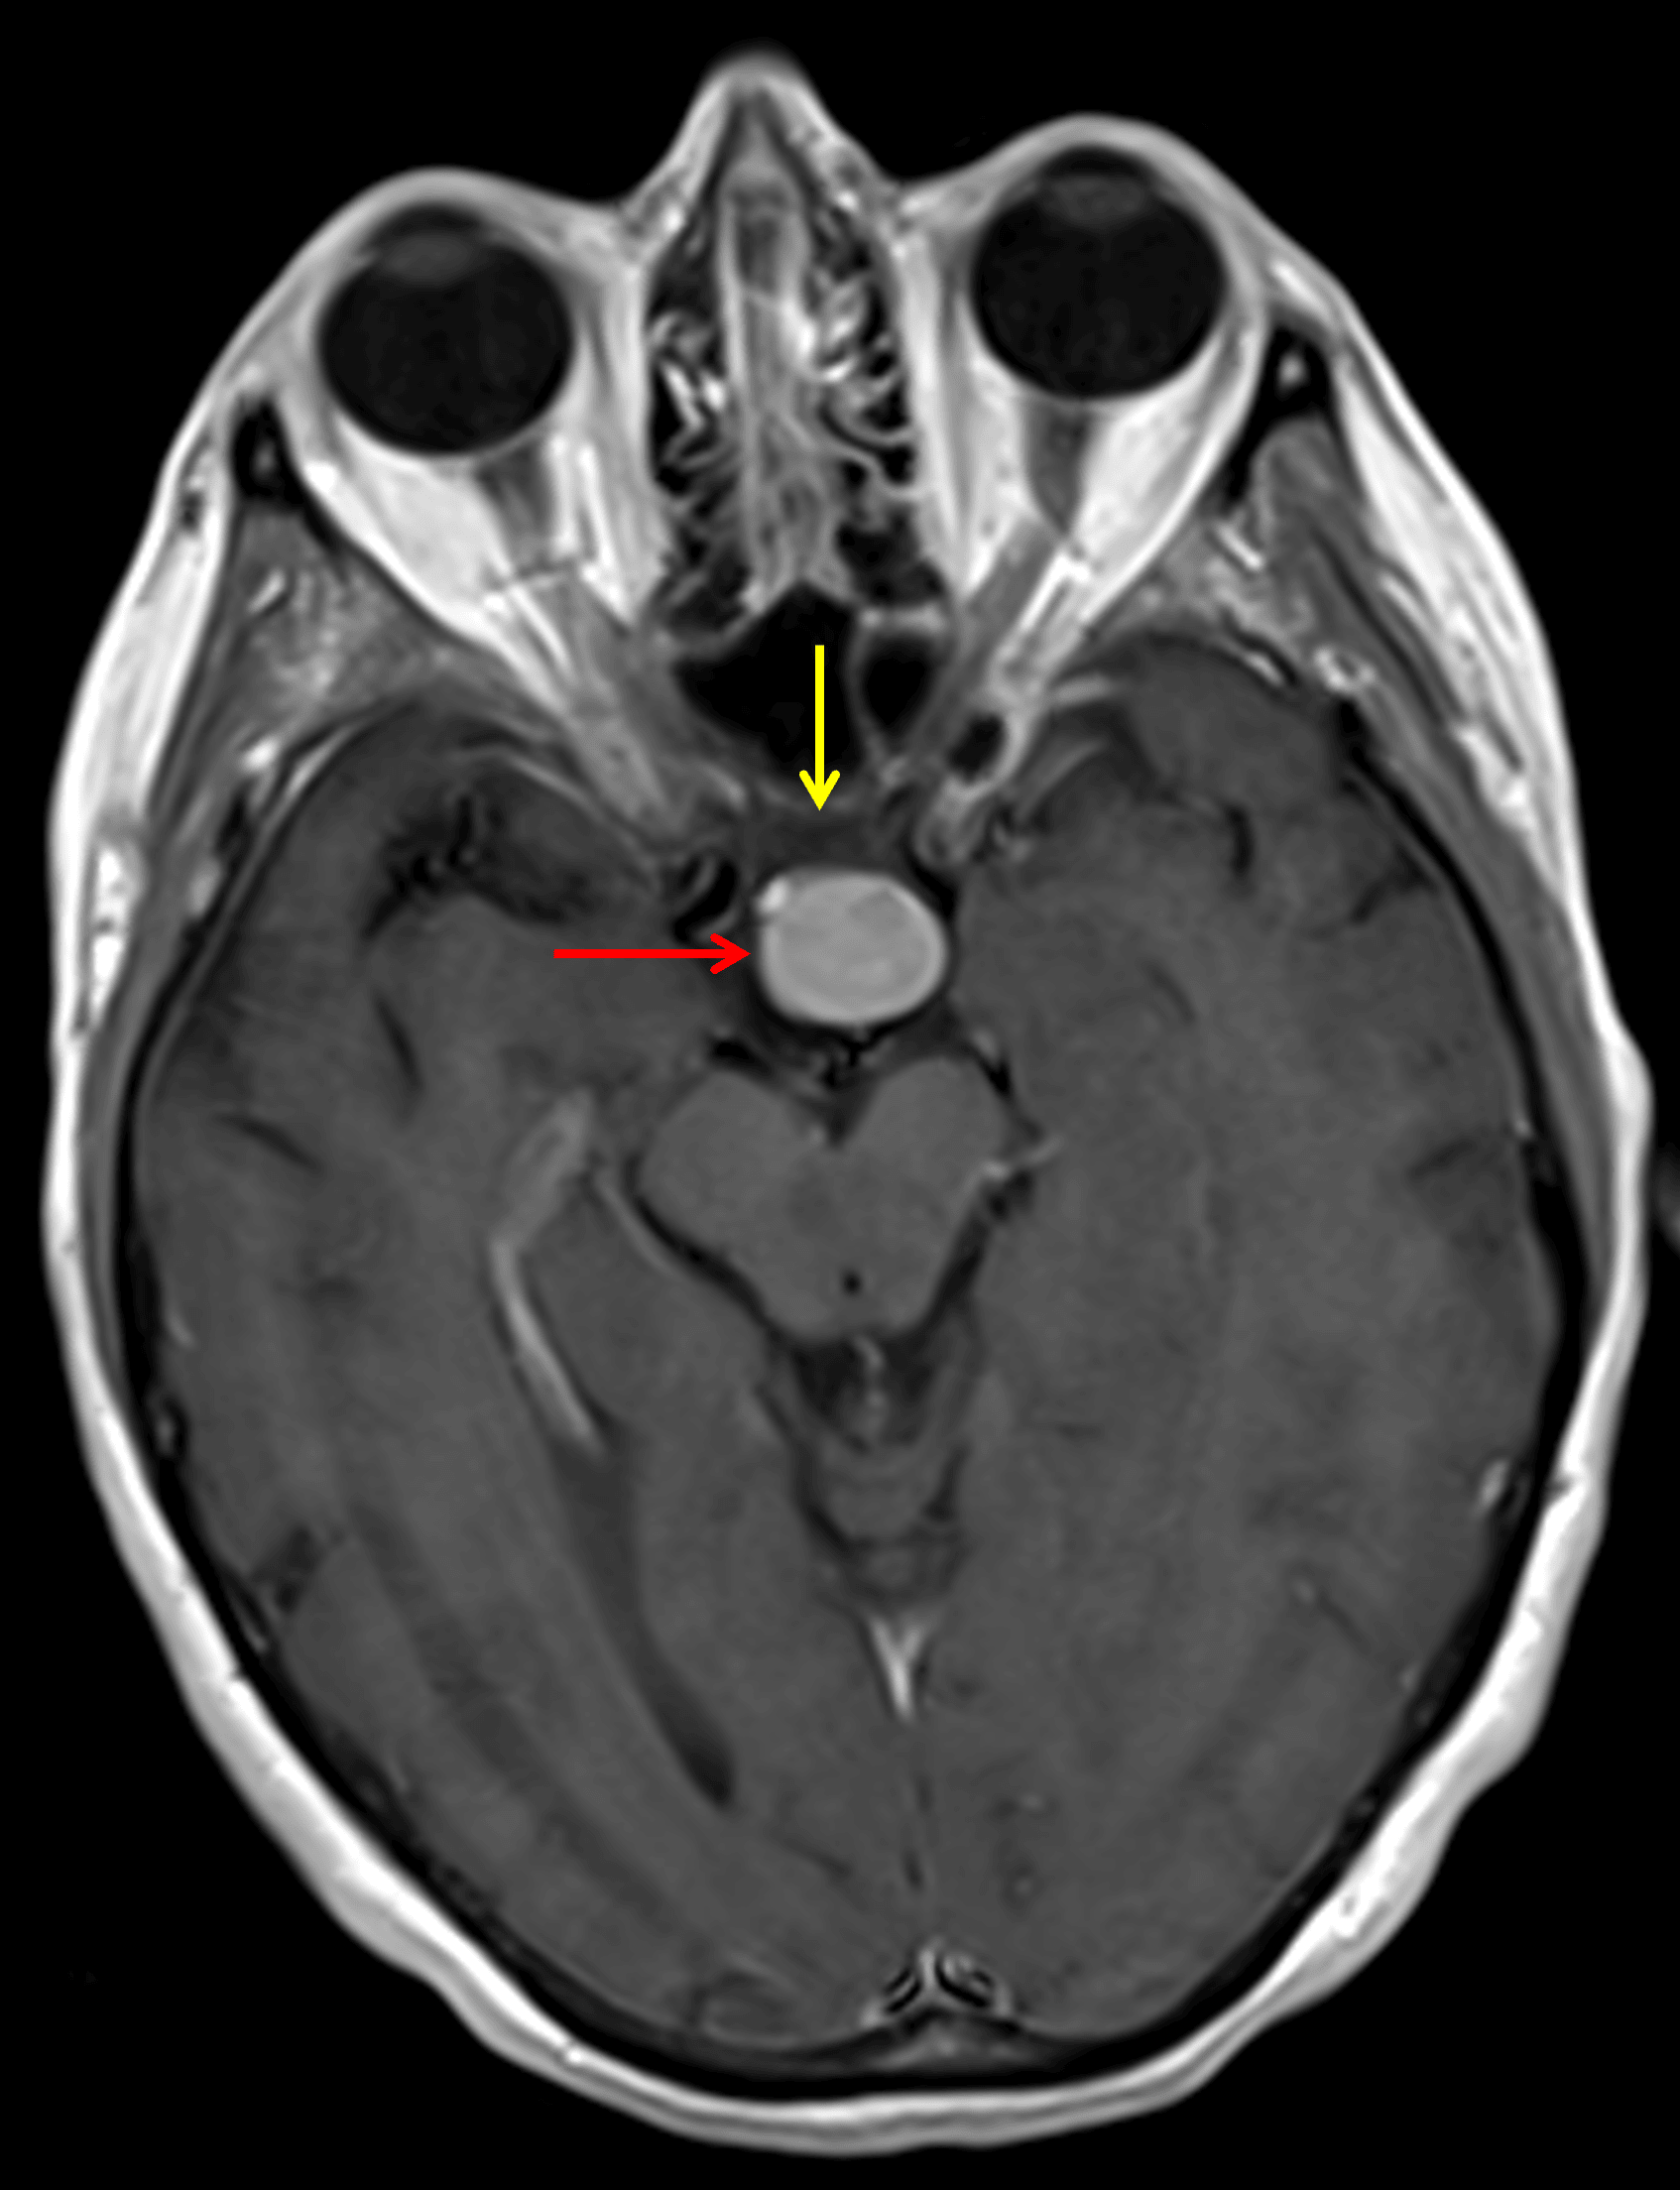

MRI

- T1/T2/FLAIR isointense, diffusely enhancing suprasellar mass measuring 1.8 x 1.4 x 1.7 cm

- Predominantly peripheral corresponding susceptibility artifact corresponding with calcification seen on CT

- The mass is centered on the pituitary stalk and is seen separate from the pituitary gland

- The mass contacts the optic tracts and posterior aspect of the optic chiasm

Diffuse corresponding enhancement (red arrow). The mass contacts the posterior aspect of the optic chiasm (yellow arrow).